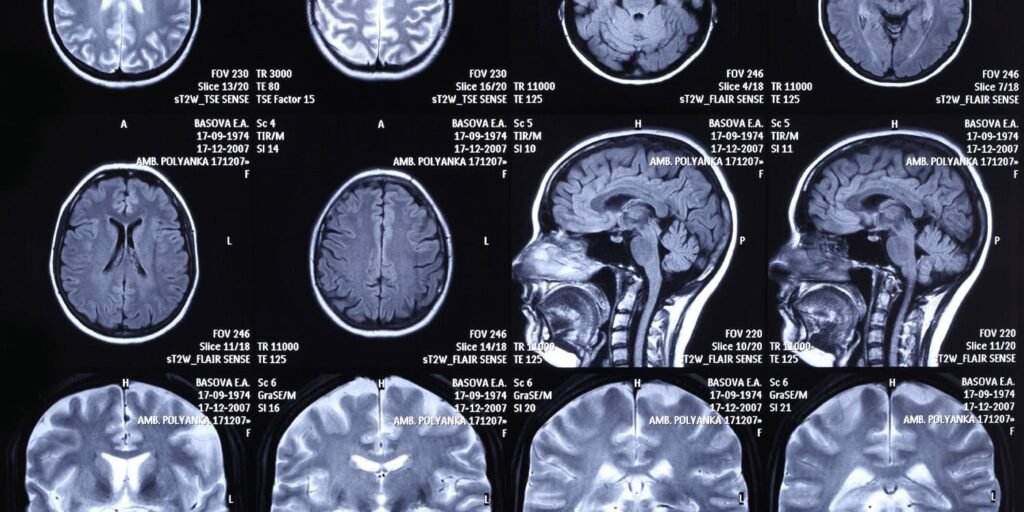

Participants were placed in a functional magnetic resonance imaging scanner. This machine uses a powerful magnetic field to track blood flow in the brain as it occurs. When certain areas of the brain work harder, they require more oxygen, and the scanner detects these subtle changes in blood oxygenation to map neural activity.